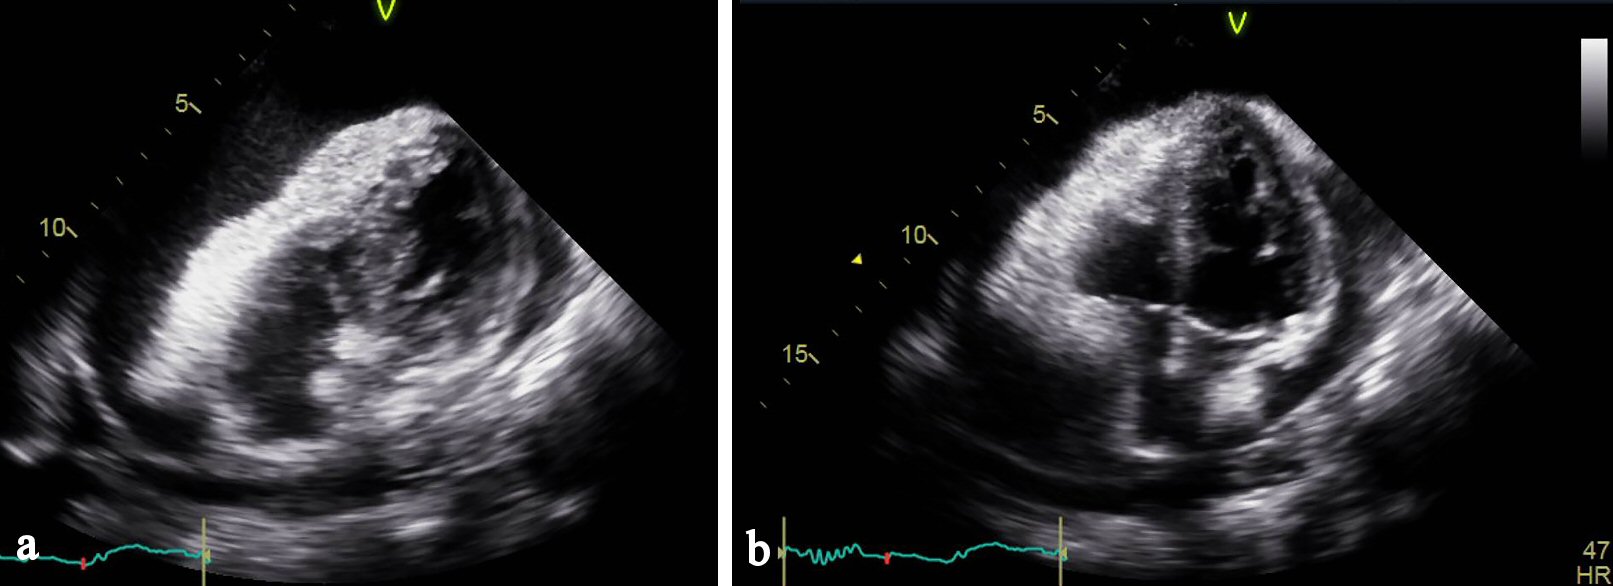

Figure 8. (a) Echocardiogram apical view showing right ventricular collapse in diastole. (b) Echocardiogram apical view showing right atrial collapse in diastole.